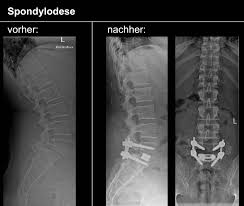

Besserung der Beschwerden bei gebeugter Körperhaltung und Hinsetzen. Es sind aber auch Operationen im Sinne einer Dekompression einer Entlastung möglich.

Dadurch zeigen sich vor allem ausstrahlend Beschwerden. Ich habe aber sehr gute Erfahrungen mit Akupunktur zur Schmerzbehandlung gemacht. Dass man Spinalkanalstenose-Operationen gut. Brauchst nur einen guten Therapeuten der sich damit auskennt. Meine Schmerzen die in die Beine ausstrahlten waren sofort nach der OP weg. Was sind die Beschwerden bei einer Spinalkanalstenose L4L5. Die wichtigsten Tipps im Umgang mit Spinalkanalstenose. Die Betreuung während meines dreitägigen Aufenthalts in der Klinik sowohl durch Dr. Grundsätzlich kann diese mit konservativen Methoden behandelt werden.